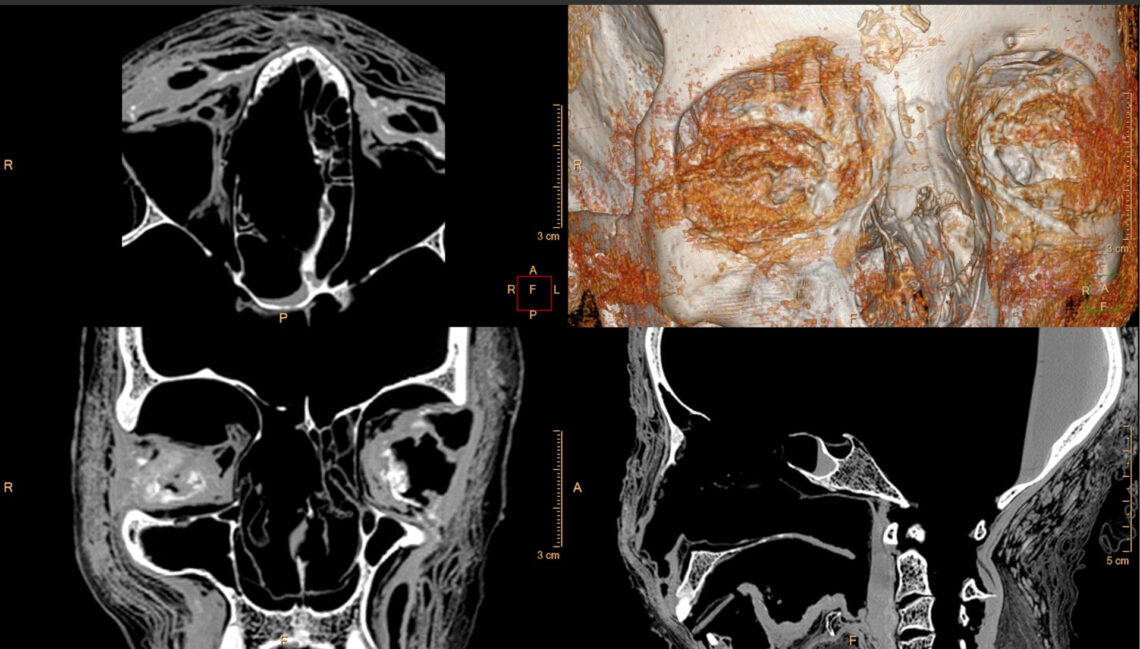

A set of objects in the the mummy’s pelvis, interpreted as the alleged fetus. A 3D reconstruction of the entire and reconstructed 2D cross-sections through the pelvis packages. CT scan and postprocessing: Ł. Kownacki